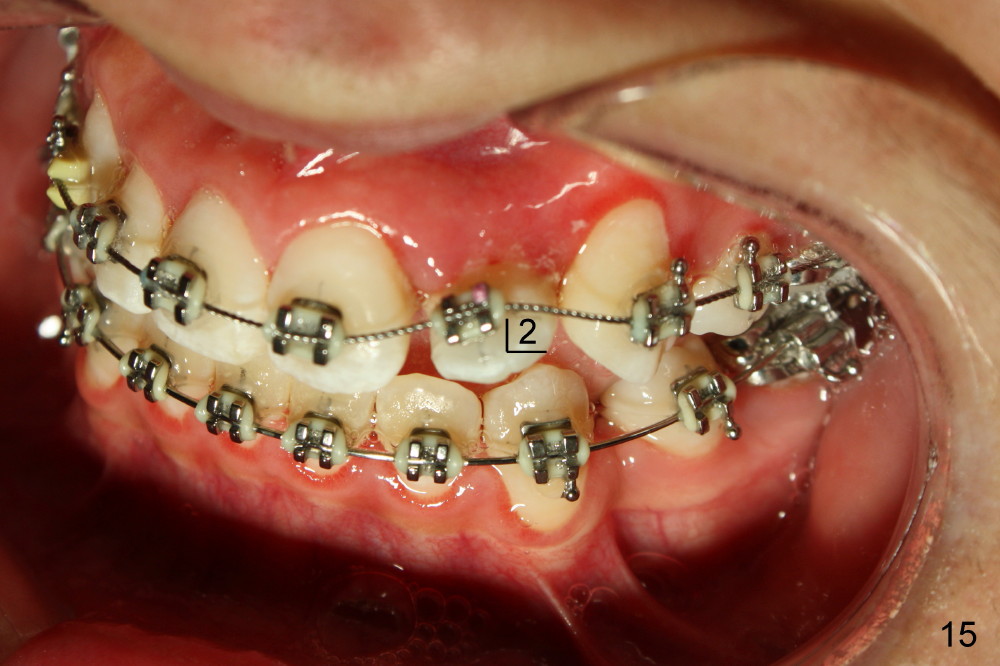

Seven months of treatment, the dental midlines coincide (Fig.13 dashed lines). Extraction spaces have been closed or being closed (Fig.13-15). UL 2 has been moved into the arch (Fig.13,15,16). But the alignment needs to be improved with arch wire sequence for a second time starting with .0175 twisted wire (Fig.13-16).